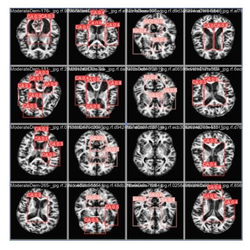

Ressonância magnética - pesquisa IA e Alzheimer 3

Tecnologia e saúde

Pesquisa usa inteligência artificial para auxiliar na detecção do Alzheimer

Estudou aliou processamento digital de imagens e modelos de IA para identificar microlesões no cérebro em exames de ressonância magnética